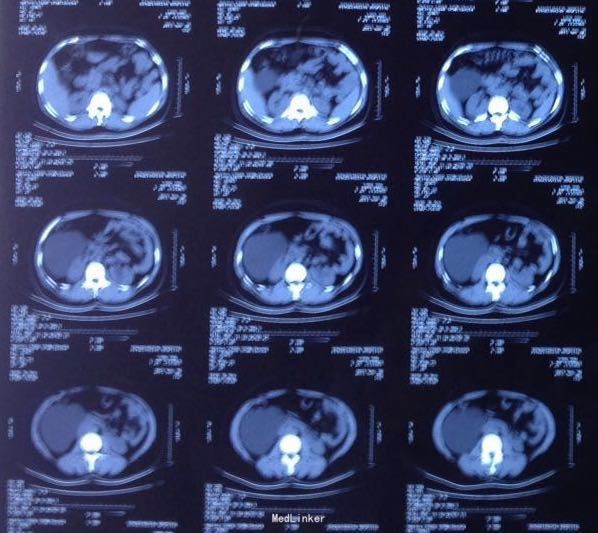

查体:心肺未见明显异常,腹软,下腹部有压痛,无明显反跳痛,双肾区无叩痛,直肠指检距肛6 cm以内未及肿块,直肠前壁处有触痛。尿常规:WBC + +。精液常规:精子活动力偏弱,WBC +。血液相关检查无明显异常。B超:盆腔囊性包块、右肾窝未见肾脏、左肾代偿性增大。CTU:右肾缺如,盆腔巨大囊肿。MRI: 盆腔巨大囊性包块,大小约62 mm×50 mm×110 mm;盆腔少量积液。静脉肾孟造影(IVP):左肾分泌功能良好,右肾缺如。膀胱镜检查:未找到右侧输尿管开口,左侧输尿管开口正常,喷尿清。后尿道未见异常。术前诊断:盆腔巨大囊肿伴右肾缺如,尿路感染。

患者术前予抗感染治疗2周控制尿路感染。术前留置导尿管保持引流通畅,头低脚高仰卧位,脐下纵行切开约2 cm,插入气腹针,充气后置入10 mm 套管,右侧麦氏点置入12 mm套管,左侧麦氏点对应处置入5 mm套管,右侧腹直肌外缘置入5 mm套管。进入腹腔后拨开肠管,切开右侧后腹膜,见右肾右输尿管缺如。腹膜后及盆腔见巨大囊性肿块,囊肿与周围组织粘连明显。仔细游离囊肿至膀胱颈部前列腺后方,见囊性肿物止于前列腺尖部后方,双侧精囊完整。囊肿与后尿道不相通。完整切除囊肿。囊肿内囊液清,囊壁光滑。

手术成功,手术时间100 min,术中出血150 ml。术后给予抗生素治疗,恢复良好。术后第4天患者正常进食并下床活动。术后第10天出院。术后病理报告:苗勒管源性囊肿伴感染。术后3个月复查CT,手术部位未见明显肿块复发。术后随访至今,症状均消失,囊肿无复发。